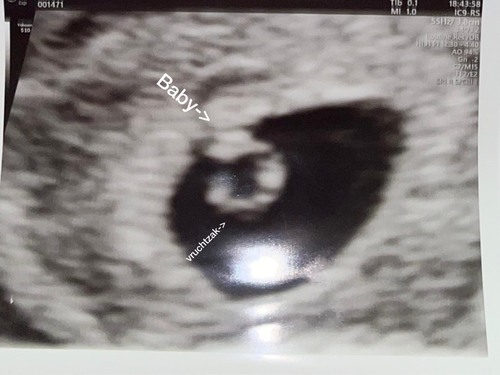

Vandaag eerste echo gehad 5weken 4dagen vruchtzakje met vruchtje en klein knipperend hartje